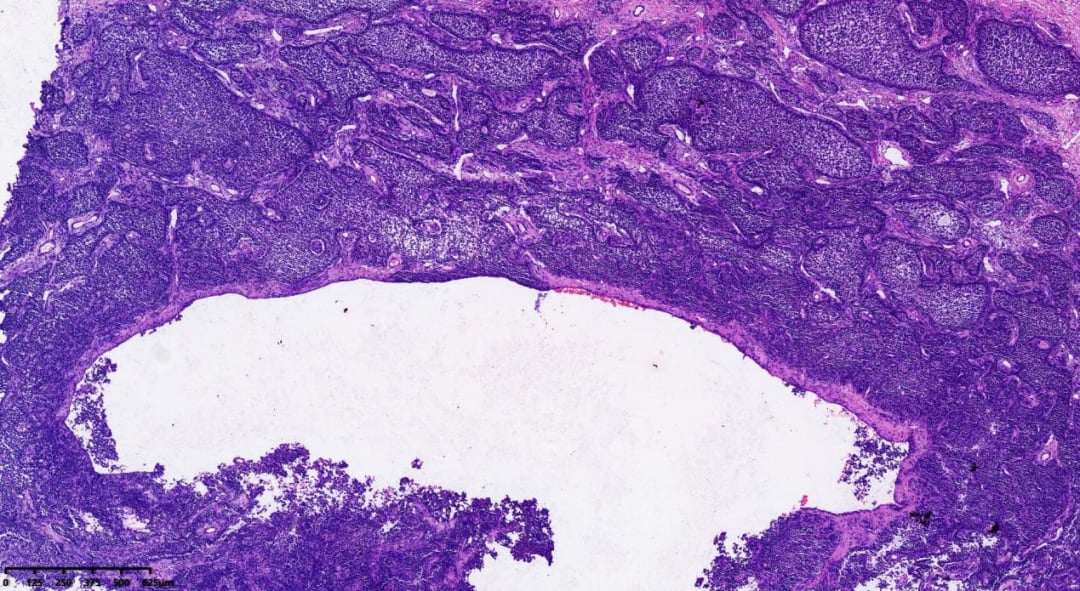

在后续的大体检查中,医生发现患者的卵巢大小显著增大,达到12×10×6cm,切面呈实性,颜色介于灰白与灰黄色之间,质地较软,并带有完整的包膜。这些宏观特征为后续的病理诊断提供了重要线索。

出现囊性变区域

可见间质分隔

病理学特征:大体与组织学

- 大体病理学:多数AGCT为单侧性,表面光滑或呈结节状,通常包膜完整。肿瘤大小差异显著,平均直径约12cm,切面呈囊实性或实性,颜色多为灰黄色,质地柔软。多数肿瘤可见出血和灶性坏死,囊性区域可呈多房或单房,内含浆液或陈旧性出血。